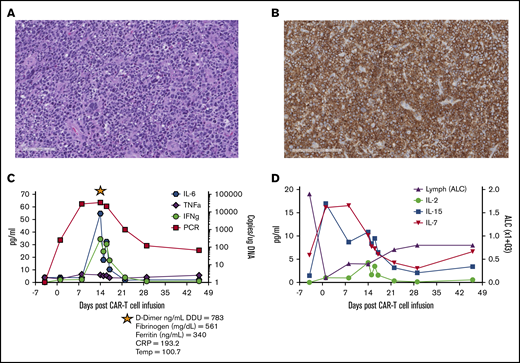

Pre–CAR-T diagnostic biopsy, CD30CAR-T expansion, and detection of homeostatic cytokines. Hematoxylin and eosin stain (A; scale bar, 100 μm) and CD30 antibody stain of the tumor biopsy before CAR T-cell therapy (B; scale bar, 200 μm). (C) Detection of CD30 CAR T-cell molecular signals by quantitative polymerase chain reaction (qPCR) and of the indicated cytokines over the course of the first 6 weeks after infusion. The star indicates evaluation of the listed parameters during the CRS event. (D) Detection of IL-2, IL-7, and IL-15 in the plasma and lymphocyte counts over the course of the first 6 weeks after infusion. ALC, absolute lymphocyte count; CRP, C-reactive protein; DDU, D-dimer unit; IFNg, interferon-γ; TNFa, tumor necrosis factor-α.

Pre–CAR-T diagnostic biopsy, CD30CAR-T expansion, and detection of homeostatic cytokines. Hematoxylin and eosin stain (A; scale bar, 100 μm) and CD30 antibody stain of the tumor biopsy before CAR T-cell therapy (B; scale bar, 200 μm). (C) Detection of CD30 CAR T-cell molecular signals by quantitative polymerase chain reaction (qPCR) and of the indicated cytokines over the course of the first 6 weeks after infusion. The star indicates evaluation of the listed parameters during the CRS event. (D) Detection of IL-2, IL-7, and IL-15 in the plasma and lymphocyte counts over the course of the first 6 weeks after infusion. ALC, absolute lymphocyte count; CRP, C-reactive protein; DDU, D-dimer unit; IFNg, interferon-γ; TNFa, tumor necrosis factor-α.

Treatment with lymphodepletion and infusion of CD30 CAR T cells was well tolerated, with grade 3 or higher toxicities limited to lymphopenia during the first 6 weeks, which was most likely related to lymphodepleting chemotherapy. The patient developed grade 1 CRS on day 12, which corresponded to the peak of CAR T-cell expansion and increased inflammatory cytokines, such as interleukin-6 (IL-6) and interferon-γ in the peripheral blood (Figure 1C). Other CRS-related parameters included elevated levels of C-reactive protein, ferritin, fibrinogen, and D-dimer. CRS resolved spontaneously by day 15 and did not require specific therapy. Although expansion of CD30 CAR T cells in this patient was associated with an increase in the homeostatic cytokines IL-7 and IL-15 after lymphodepletion (Figure 1D), CD30 CAR T cells were no longer detectable by quantitative polymerase chain reaction 3 months after infusion.8